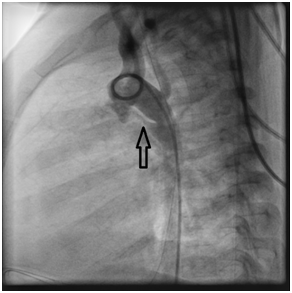

A catheter was easily passed percutaneously through the femoral vein into the pulmonary artery and aorta through the PDA. It was decided that to close the PDA with amplatzer ductal occluder type 2 size 4 by 6mm, and successfully closed (Figure 5) (Figure 6).

Figure 5 Angiogram: The device closed the PDA.

Figure 6 Angiogram: suitable device size without any leak.